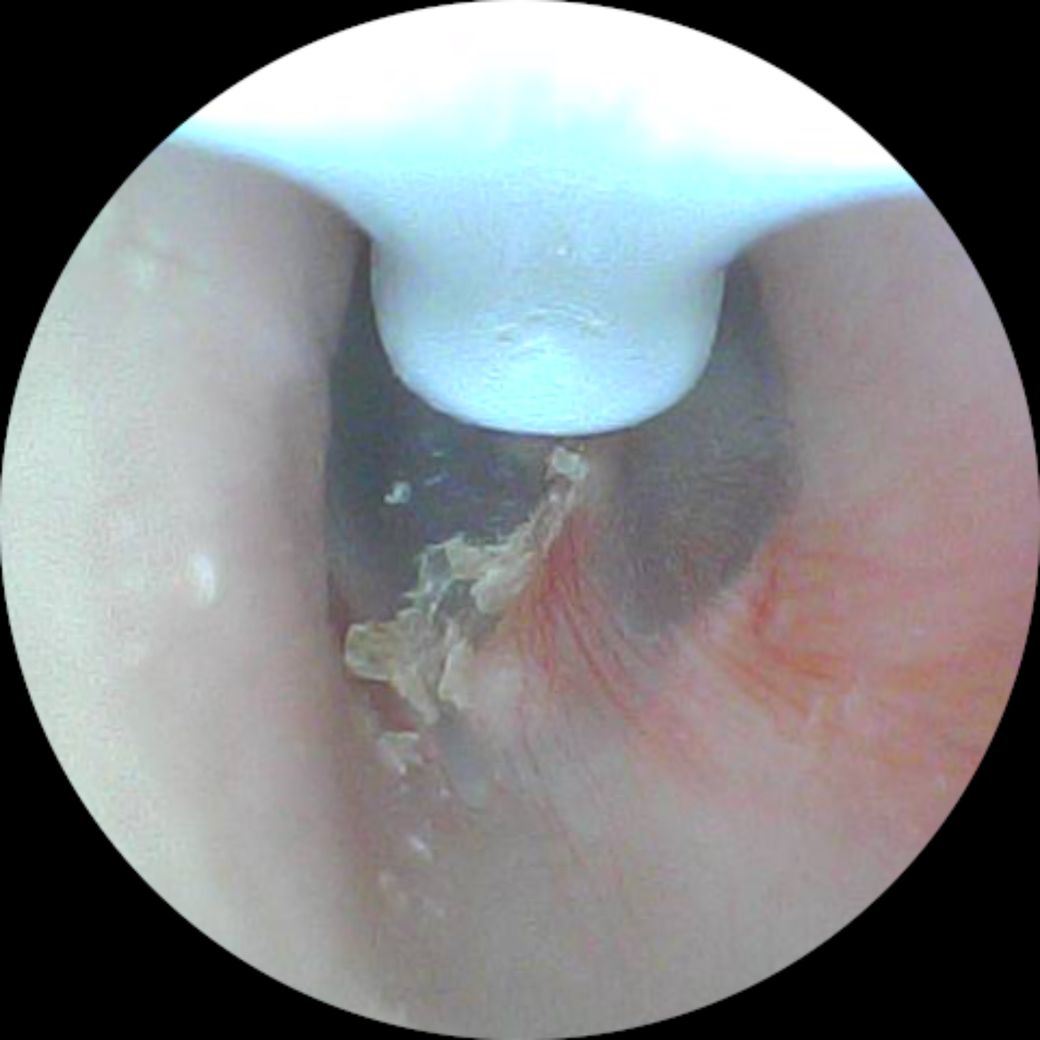

고막에 붙어 있는 귀지 뺄 수 있는 방법은 없나요

집에서 핸드폰 연결해서 귀지 팔 수 있는 귀이개 사용 중인데요 고막? 같은 막에 붙어있는지 너무 깊어서 귀이개가 잘 닫질 않고 아파서 근데 눈에 보이니 넘 거슬려요

이거 뺄 방법 없나요?

• 1번 째 사진

귀지가 고막에 붙어있는데 너무 깊어서 귀이개가 잘 닫지 않는데 눈에 거슬리시는 군요

고막에 붙어있으며 소량이네요